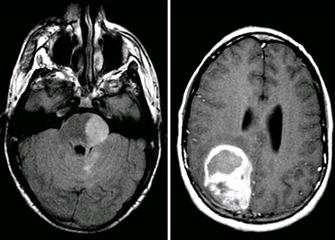

교모세포종(Glioblastoma)

악성 신경교종(Malignant Glioma)